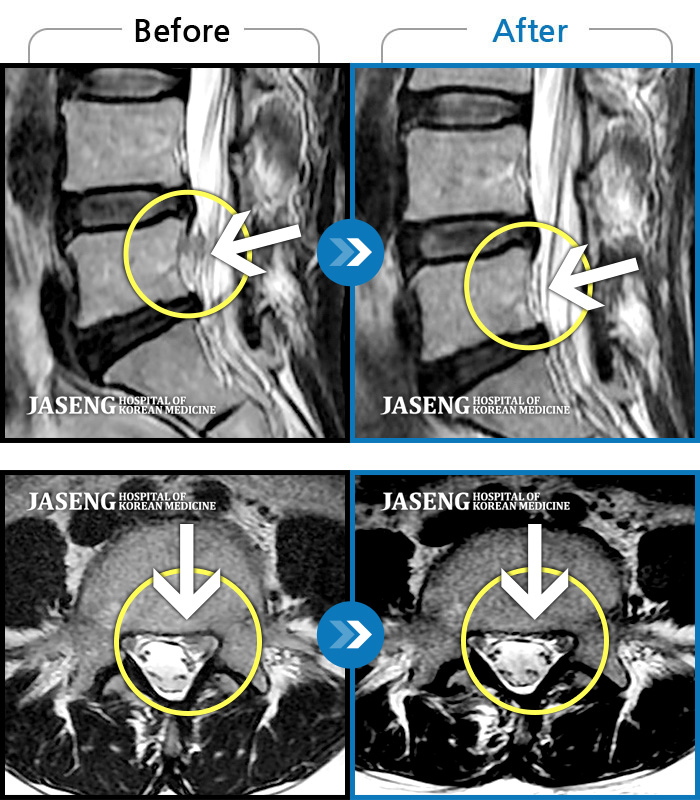

허리디스크

부천 · 신동재 원장

양쪽 허리와 골반 통증, 걸을 때 우측 다리 당김 및 통증

촬영시기

2018.04.27 ~ 2019.02.01

2019.02.21